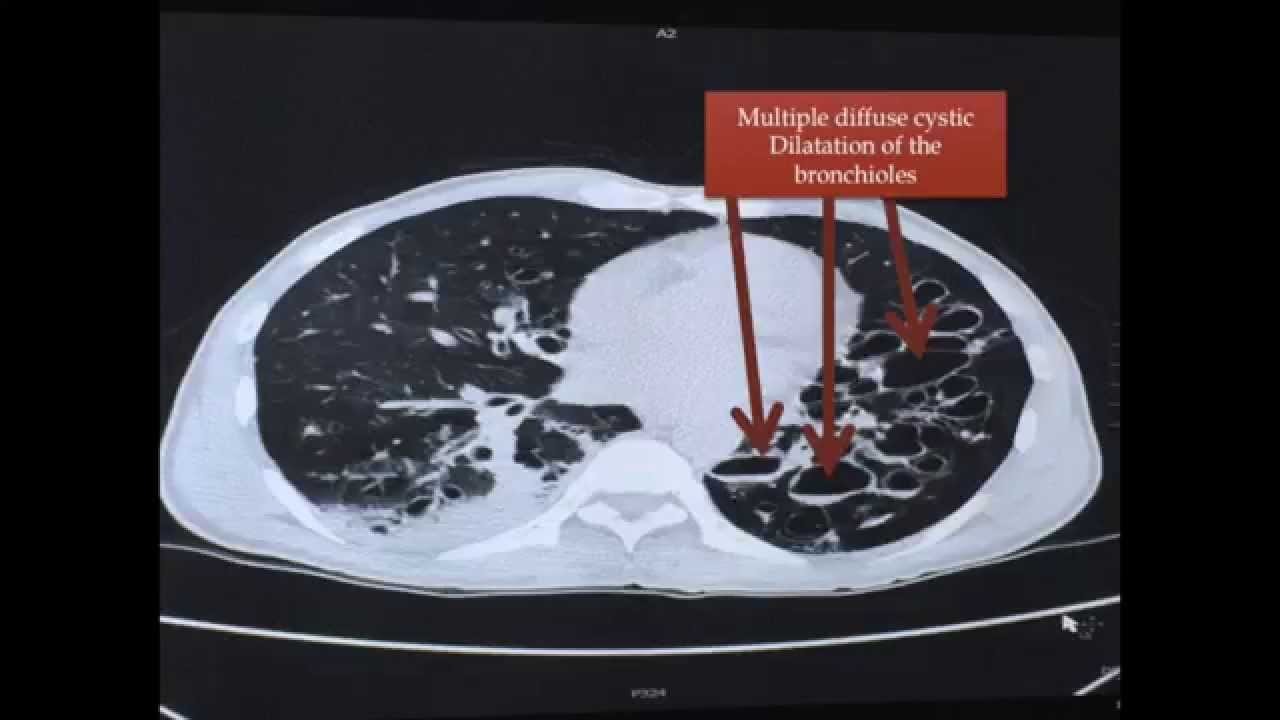

What other investigations are done for bronchiectasis?